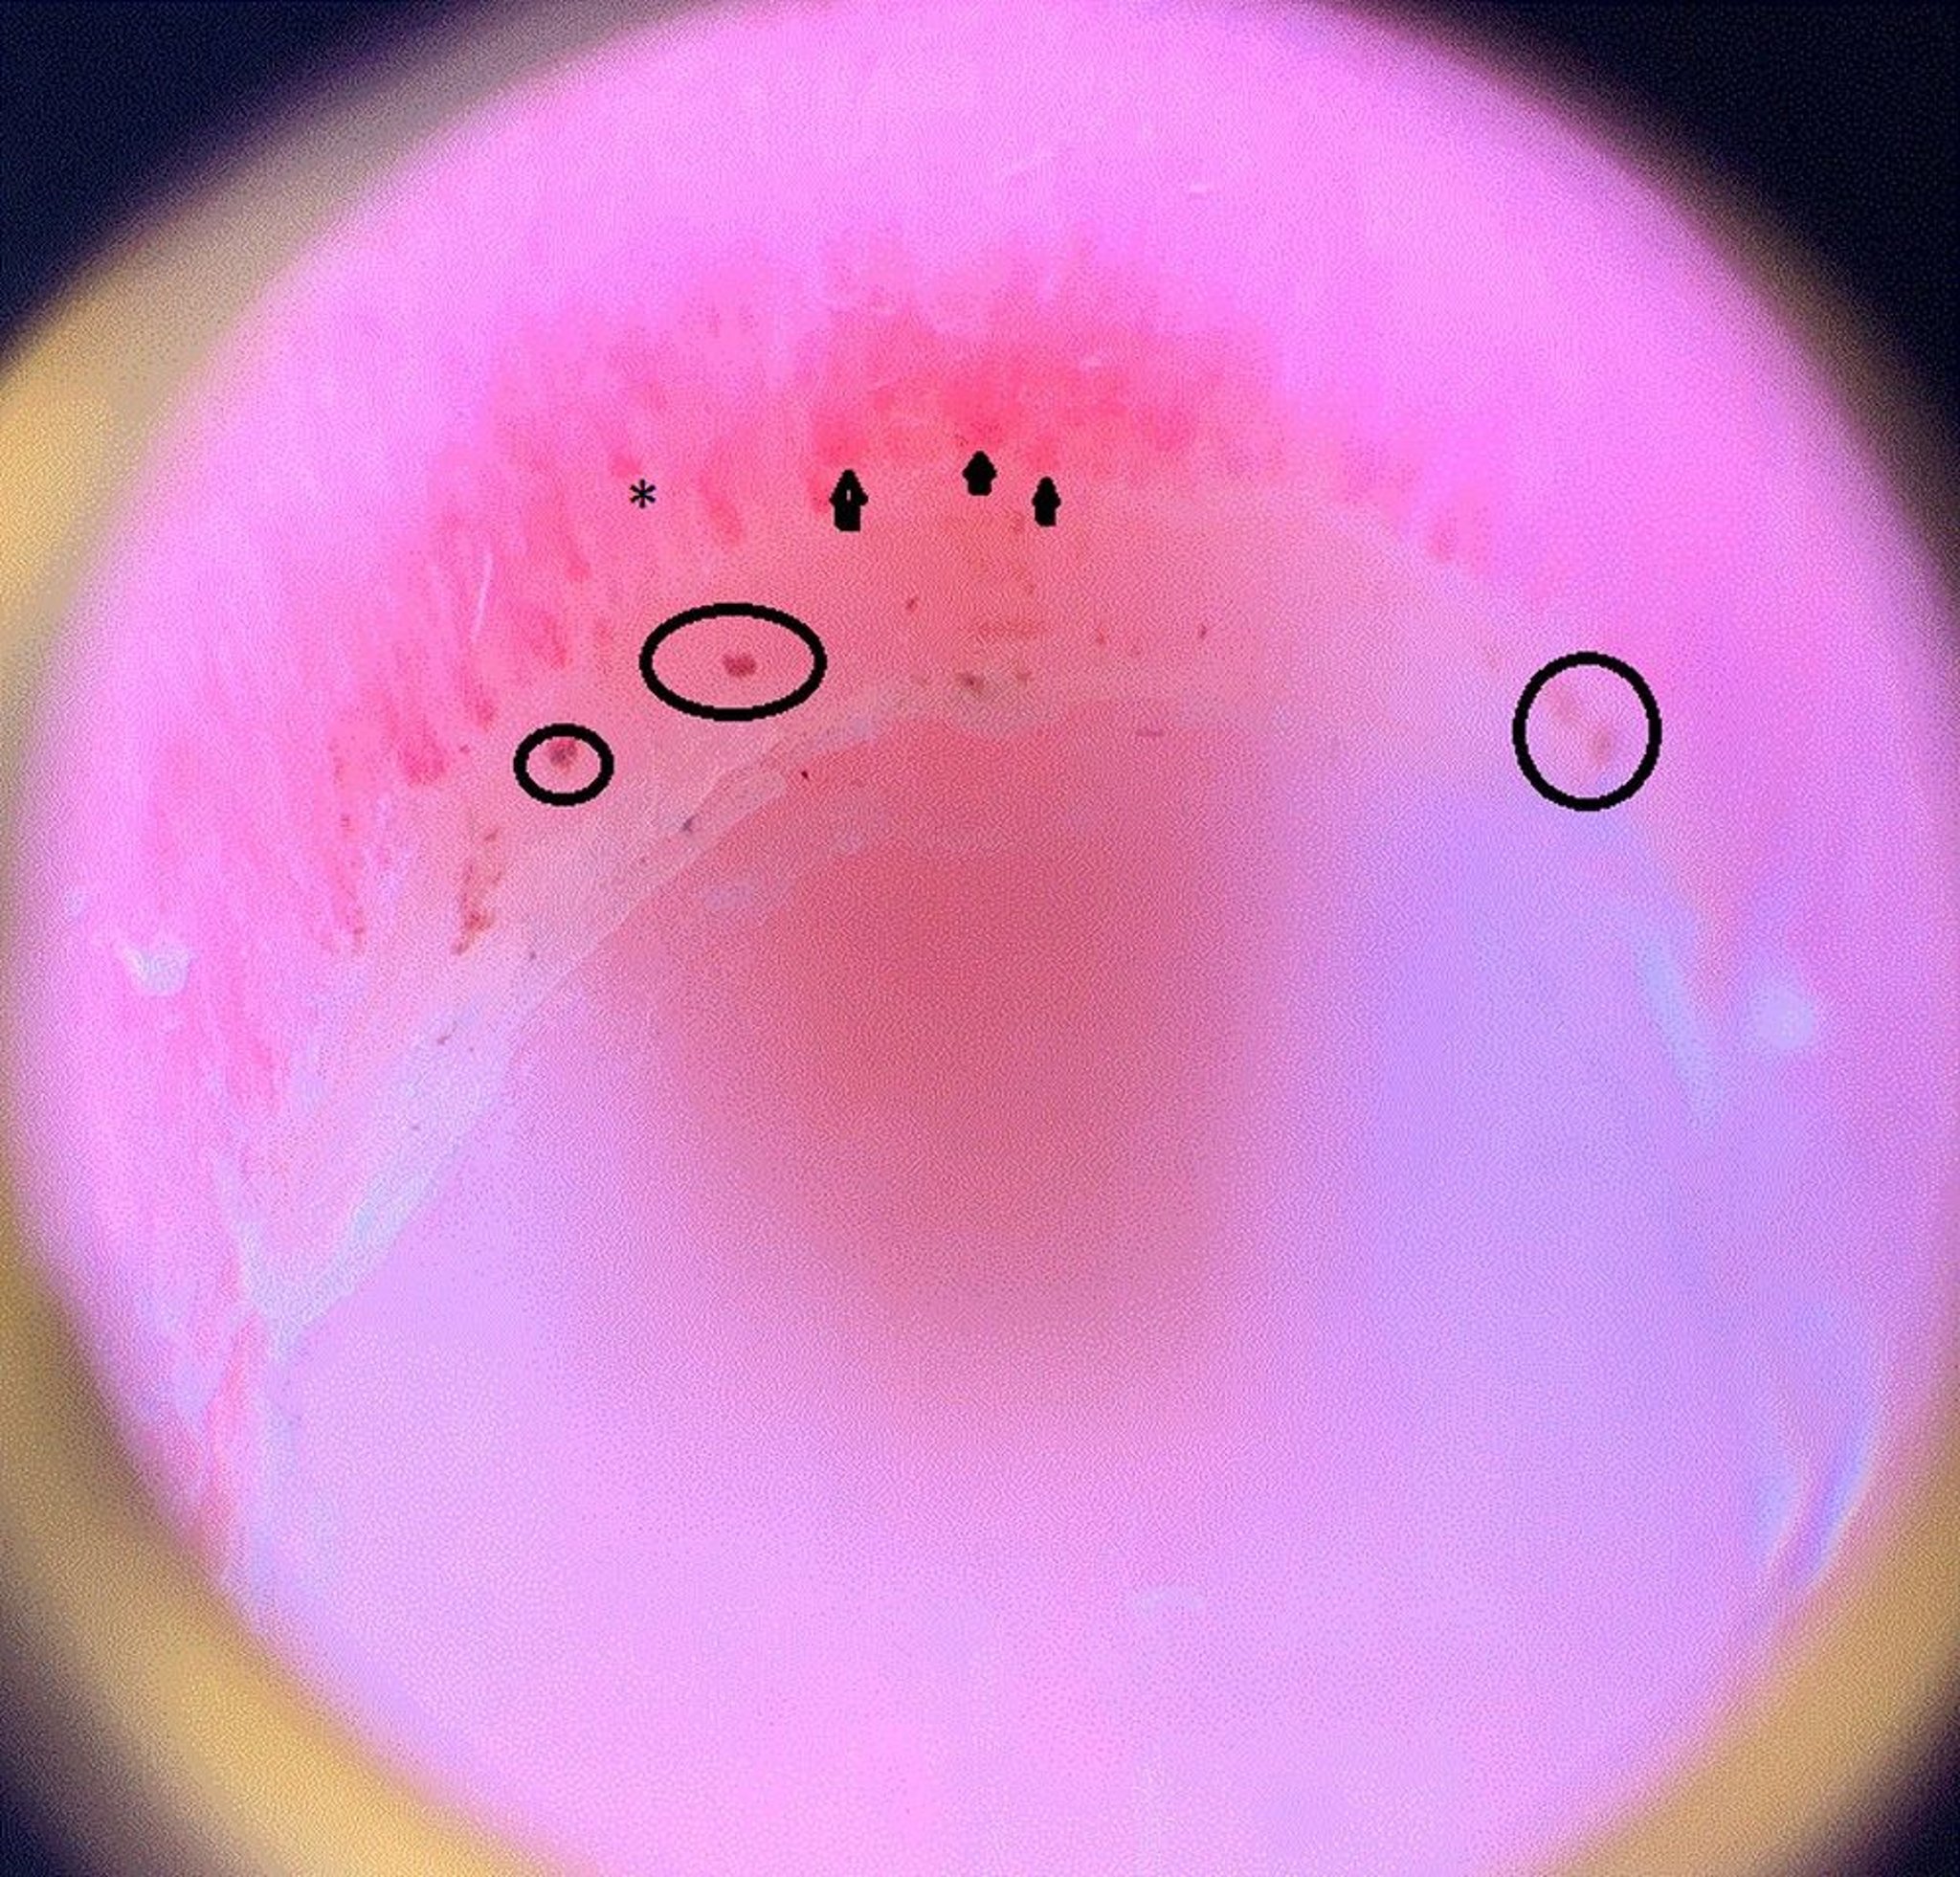

This image shows dilated capillary loops (arrowheads); a dropout area, which means the capillary ends prematurely and drops out and therefore looks shorter than the others (asterisk); and periungual hemorrhages (circles) in the nail fold of a patient with systemic sclerosis.

Image courtesy of Sanjeev Patil, MD.